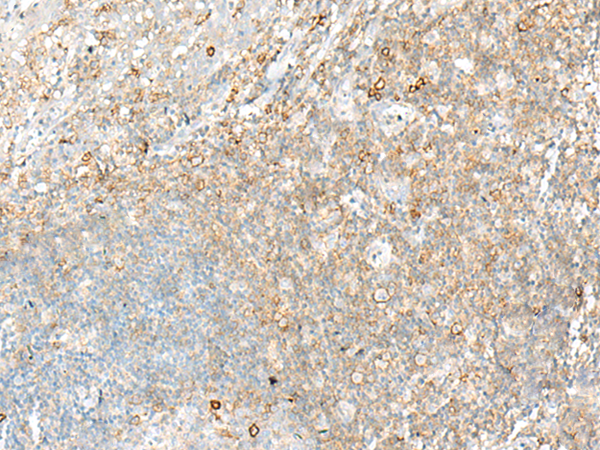

分类: 科研抗体货号: P13578别名: SS1; DRB1; HLA-DRB; HLA-DR1B应用: IHC反应种属: Human